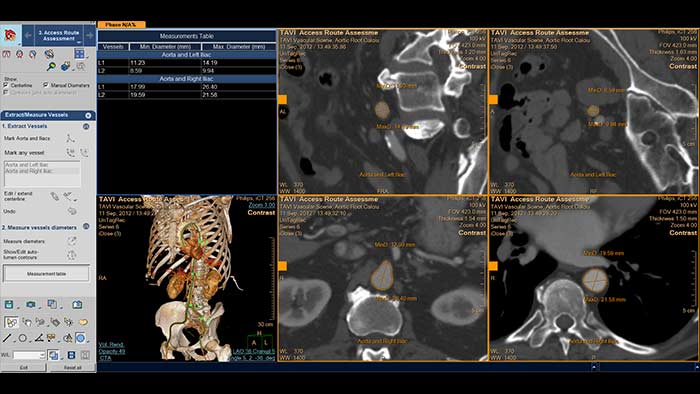

Évaluation automatisée de la voie d’accès IntelliSpace Cardiovascular

Dimensionnement de remplacement valvulaire aortique percutané entièrement automatisé avec HeartNavigator

Le parcours d’un patient TAVI avec IntelliSpace Cardiovascular